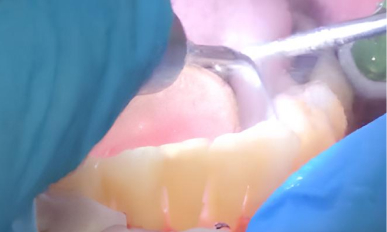

Triplo-2.jpg

3. Дезинфекция: После лазерной обработки область лечения тщательно промыли антисептическим раствором для удаления остатков бактерий и воспалённых тканей.